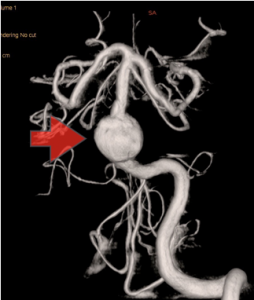

当科で治療した年々大きくなった大型脳底動脈瘤の3次元脳血管撮影像です。脳動脈瘤と周囲の血管の状態が非常によく分かるため、術前に十分な検討が可能でした。

正常の脳底動脈の血流は維持されている。